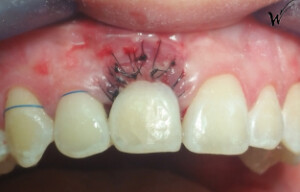

Après la guérison des tissus mous (gencive) et durs (os alvéolaire), la couronne céramique esthétique a été installée sur l’implant.

Le maintien de l’esthétique du sourire dépend en grande partie de la reconstruction des tissus gingivaux entourant la couronne céramique esthétique et de l’os autour de l’implant.